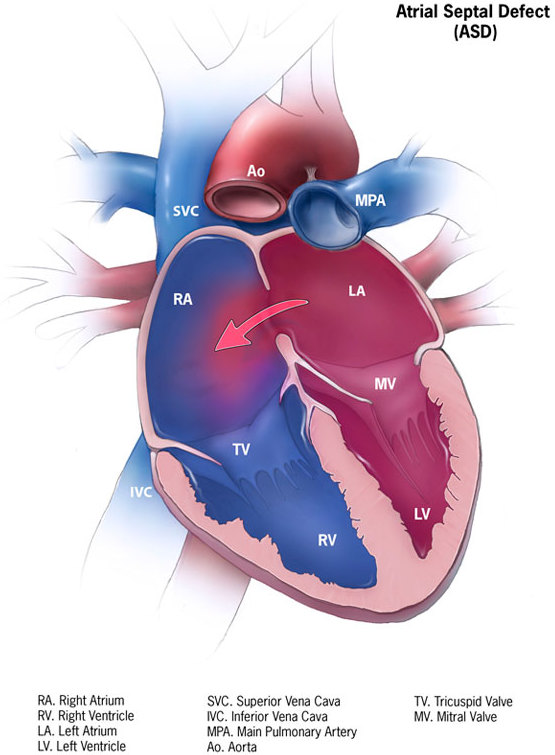

Atrial Septal Defect (ASD)

An atrial septal defect (ASD) is a hole in the wall that separates the right and left atria.

Ostium secundum is the most prevalent (90 percent of cases) cause of atrial septal defect (ASD).

Down syndrome is linked to the osteoid primum type of atrial septal defect (ASD).

An atrial septal defect (ASD) results in a divided S2 and a left-to-right shunt on auscultation (increased blood in right heart delays closure of pulmonary valve).

Paradoxical emboli are potential complications of atrial septal defects (ASD).